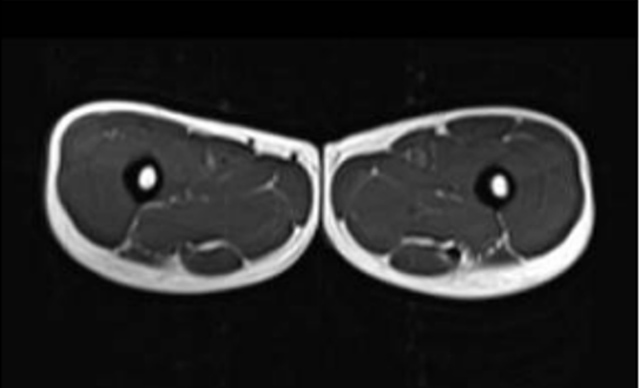

Vergleich des Oberschenkelquerschnitts eines 21-jährigen und eines 83-jährigen – weiss ist Fettgewebe

(Quelle: published online on 01.11.2019, https://doi.org/10.34045/SSEM/2014/25)

Vergleich des Oberschenkelquerschnitts eines Fettleibigen und Normalgewichtigen